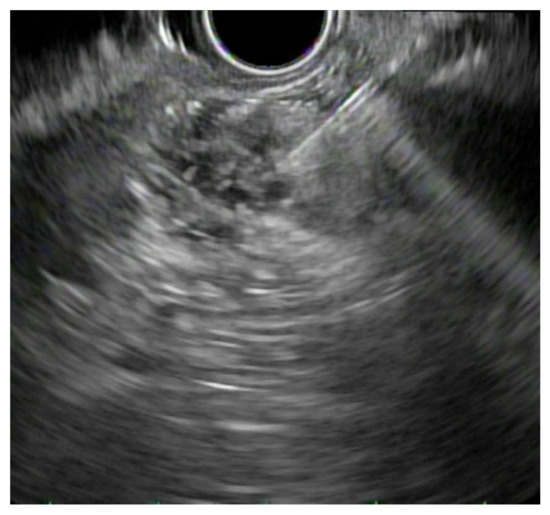

3.1. EUS vs. Percutaneous Biopsy

3.2. EUS-FNA vs. FNB